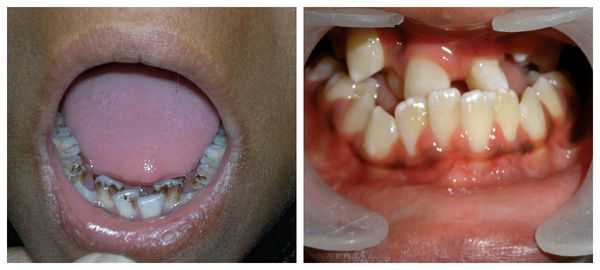

Ребёнок женского пола, возраст — 1 месяц. Вес — 3900 гр, рост — 55 см. При осмотре обнаружено, что у ребёнка уменьшена левая половина лицевого черепа (гемифациальная гипоплазия), отсутствует левая ушная раковина, на её месте имеется папиллярный вырост, ещё два выроста локализуются на левой щеке. Левый наружный слуховой проход не визуализируется. Микростомия, расщелина верхней губы, протяженностью 4 мм, справа. При осмотре ротовой полости обнаружено уменьшение левого альвеолярного отростка верхней челюсти. Физическое развитие в пределах нормы. Отклонений со стороны дыхательной, пищеварительной, мочевыделительной, половой систем не выявлено.

Коррекция косметических недостатков проводится в разном возрасте, так как она не несёт в себе опасности для жизни и развития. На удалении преаурикулярных выростов настояли родители. Вопрос о слухопротезировании будет решаться в более старшем возрасте, учитывая, что слух справа в норме. После прорезывания зубов показана ортодонтическая коррекция верхней челюсти.